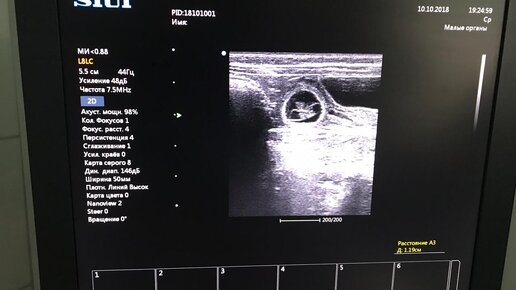

Как выглядит УЗИ беременности у кошки на ранних сроках?

Свершилось! Сегодня Узи подтвердило беременность у нашей девочки Малайки ! Не зря они с нашим красавцем Ясем так старались все три дня)) Мы уже и сами догадывались об этом: уж слишком много она стала спать и есть!) А ее округляющийся животик мы с радостью наблюдаем каждый день! УЗи беременности обычно делают на сроках не раньше 3 недель, но если УЗИ аппарат хороший, экспертного класса - то можно увидеть и раньше. Даже в 2 недели и даже - в 10 дней!!! В ветеринарной клинике "Василек" - именно такой...